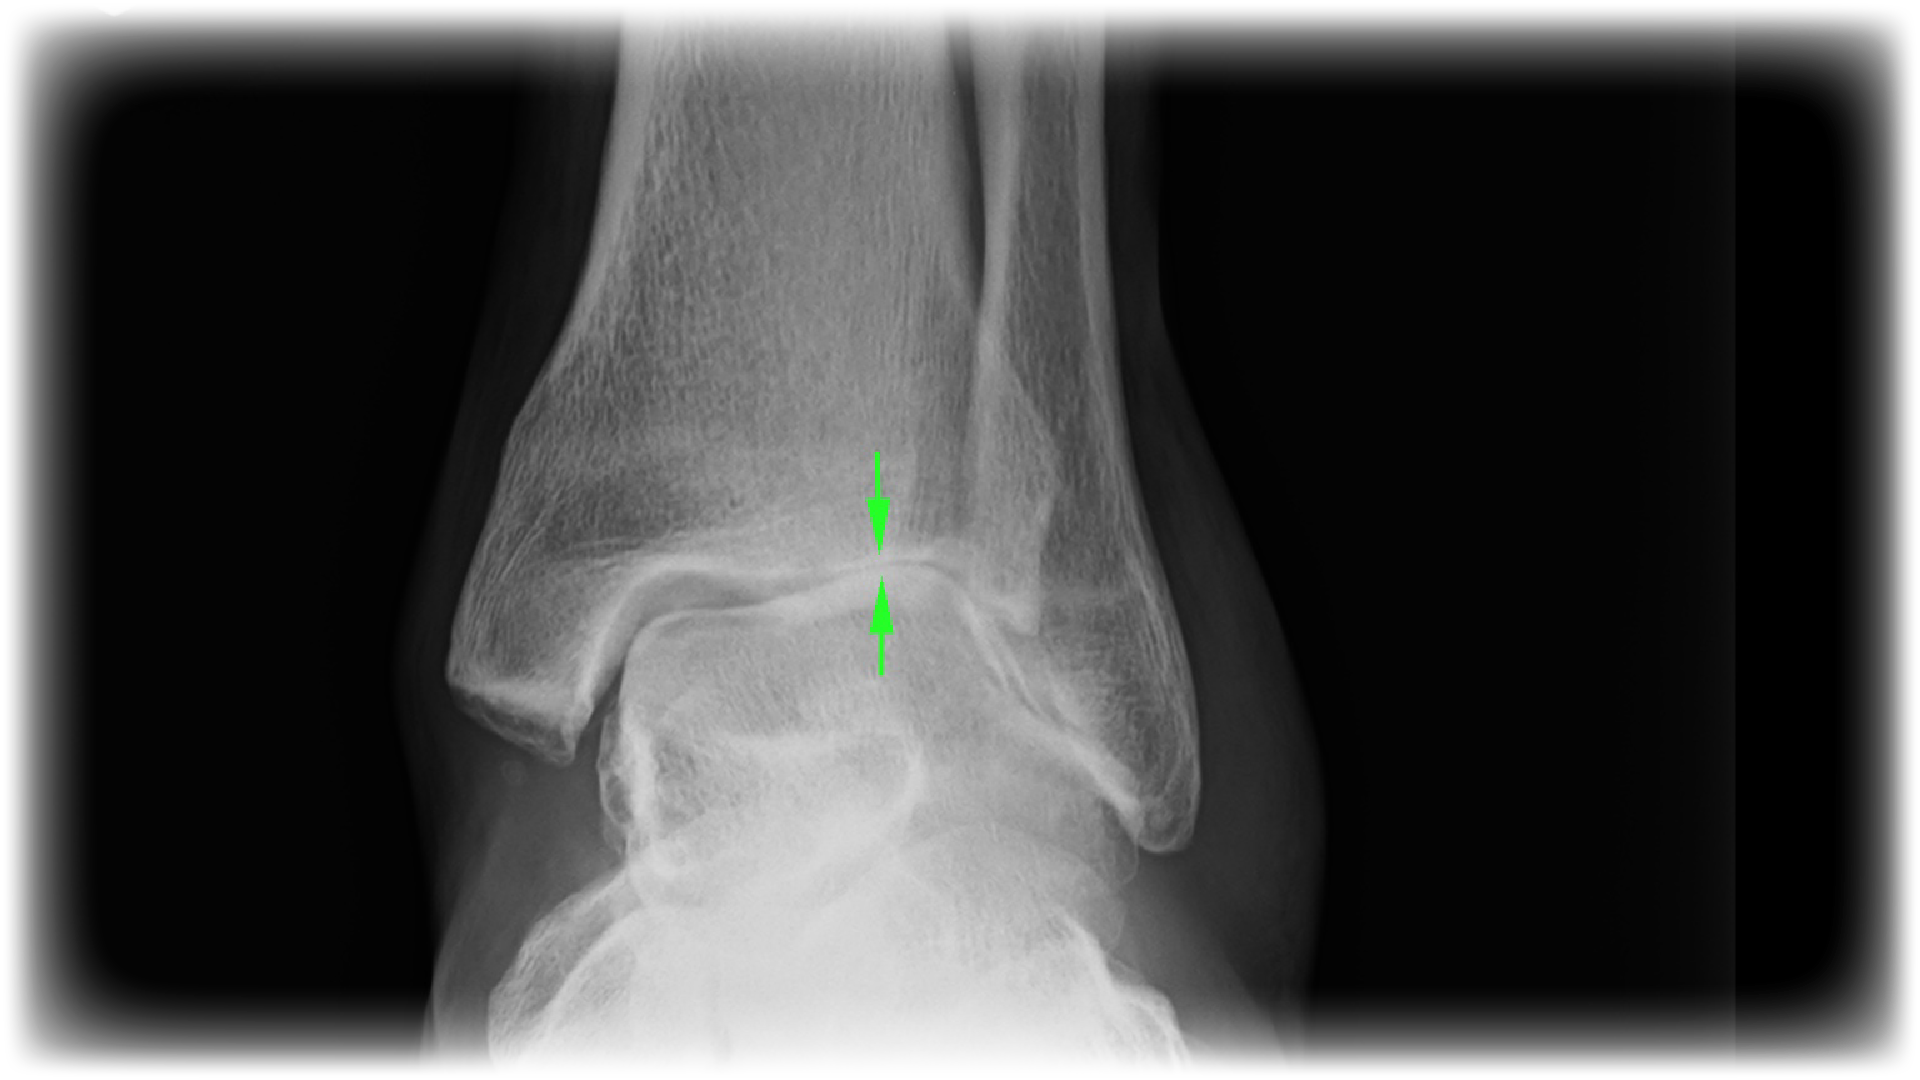

X Ray Ankle Dislocation Arthritis After Ankle Dislocation osteoarthritis of the ankle is common but it's not the only kind of arthritis that can affect the bones of the feet and ankles. posttraumatic osteoarthritis of the ankle is the primary cause of ankle arthritis. management of ankle arthritis after severe ankle trauma could pose different and difficult challenges in treatment compared. our objective was. Arthritis After Ankle Dislocation.

From www.alamy.com